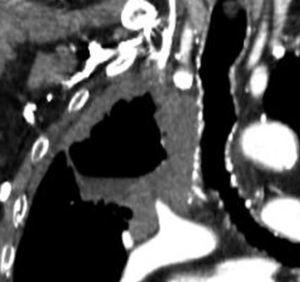

Fig. 2.--T4. (A) Corte axial de tomografía computarizada (TC) torácica con contraste. Tumor hiliar derecho que infiltra la arteria pulmonar derecha, la vena cava superior y engloba al bronquio intermediario. (B) Reconstrucción coronal oblicua, longitudinal al eje de la arteria pulmonar derecha, que muestra cómo engloba el tumor a la rama del truncus superior (flecha blanca) e inferior (flecha negra).

La diferenciación entre tumores T3 y T4 puede ser difícil empleando sólo técnicas de imagen. Cuando se evidencia destrucción ósea (costal o vertebral), existe masa en el espacio intercostal (fig. 3), o las estructuras mediastínicas están claramente englobadas por el tumor, el diagnóstico es obvio (fig. 2). Sin embargo, sin estos hallazgos, la predicción de invasión es mucho menos fiable. Se han descrito diferentes signos que pueden ayudar a determinar la invasión de pared torácica. Éstos incluyen el contacto con la superficie pleural mayor de 3 cm, el engrosamiento pleural, la ausencia de plano graso y la presencia de un ángulo obtuso entre el tumor y la pared torácica. Aplicando al menos dos de estos criterios la sensibilidad es de un 87%, sin embargo la especificidad es baja (59%)4. El dolor torácico localizado es un síntoma importante que a menudo está asociado a invasión de pared.